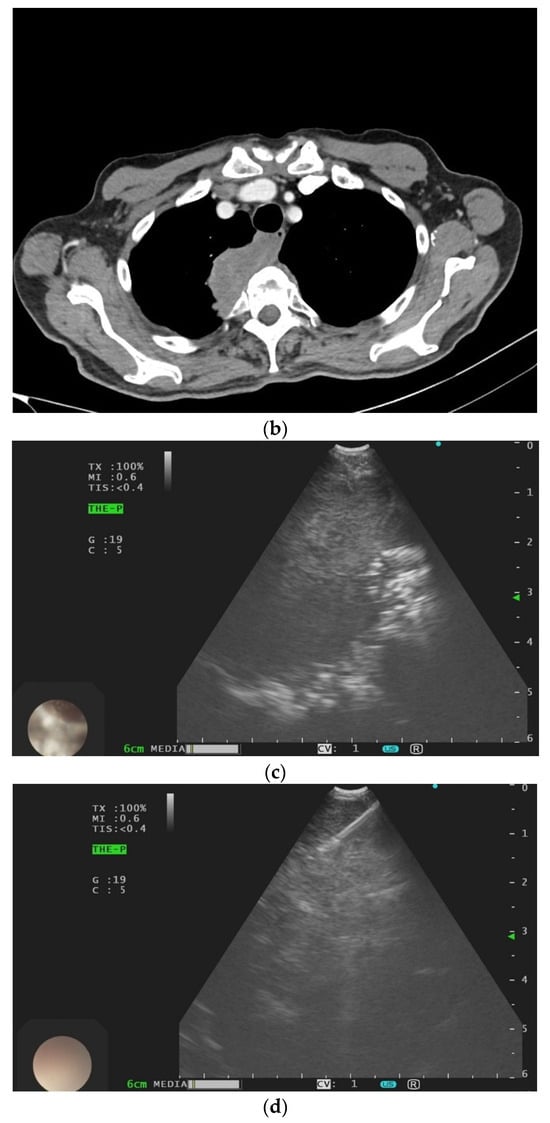

Contrast-Enhanced Ultrasound (CEUS) of the Lung and Pleura

3. Pleural Mesothelioma